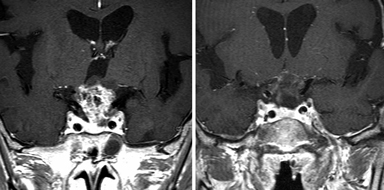

経鼻内視鏡手術の術前と術後

頭蓋底腫瘍に関しては、頭蓋咽頭腫や鞍結節髄膜腫などが対象となります。腫瘍が頭蓋内の深いところにあるため、これまでは頭を大きく開け、脳や神経、血管を押し分けて摘出する開頭手術が必要でした。しかし、腫瘍の大きさによっては鼻から手術を行うことで体の負担を少なく摘出が可能です。さらに経鼻手術では腫瘍の下からアプローチするので、脳や神経、血管などを押し分ける必要がないため、より負担が少なくなります。手術の際には、安全性を高めるためにナビゲーションや神経モニタリング、血管ドップラーを使用します。術後は翌日から歩行が可能で、問題なければ術後7日間で退院可能です。この手術における髄液漏の危険性は下垂体腫瘍の手術より高く30%と言われていますが、当院では、大腿部から採取した筋膜をパッチワークのように縫合することで髄液漏を完全に抑えることに成功しています。